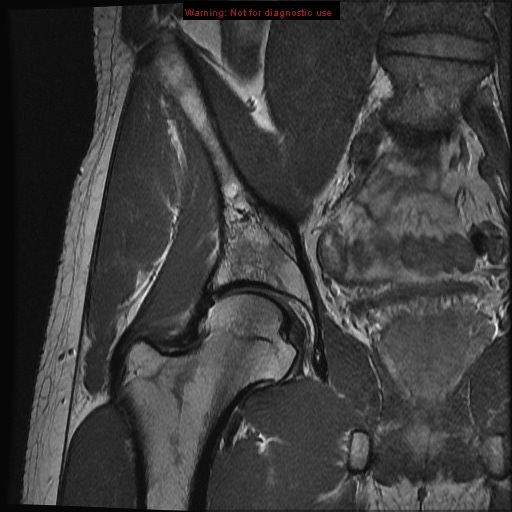

hamstring tendon

obturator internus muscle

hamstring tendon sciatic nerve

sciatic nerve

obturator externus muscle

obturator externus muscle quadratus femoris muscle

adductor magnus muscle quadratus femoris muscle

quadratus femoris muscle

rectus abdominus muscle lesser trochanter of femur

calcar femoralis

transverse acetabular ligament